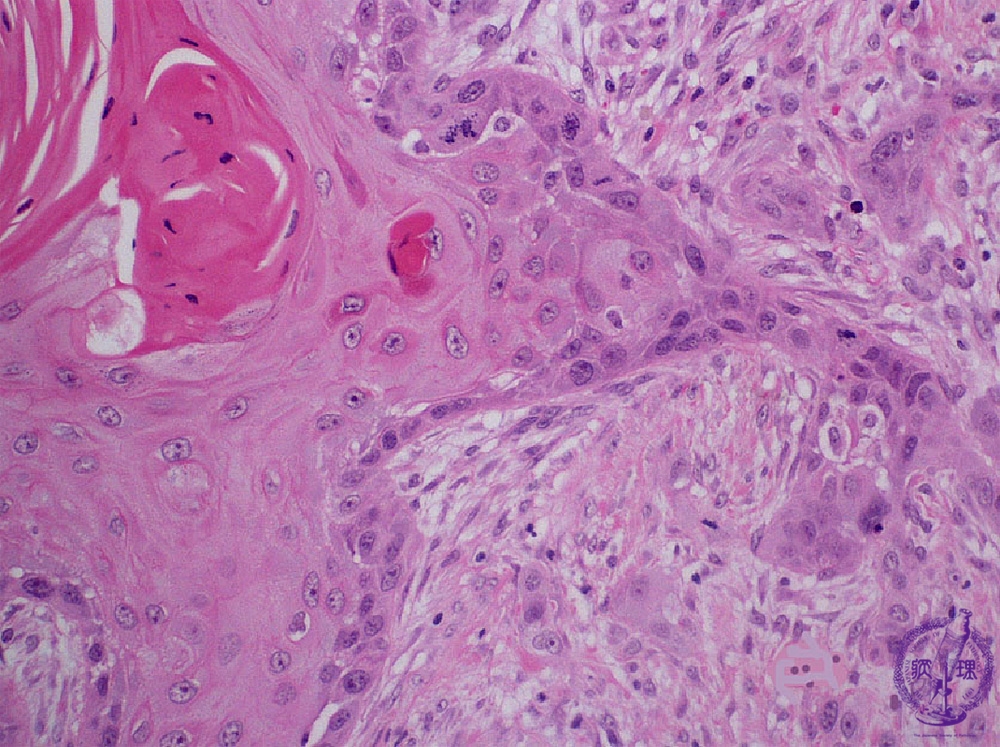

- ★(6)Oral cancer (Squamous cell carcinoma)

Microscopic finding (HE stain, high-power view):Despite exhibiting keratinization and recognizable stratified squamous cell epithelium architecture, there are characteristic features of cancer such as nuclear pleomorphism and atypical mitoses (arrow).